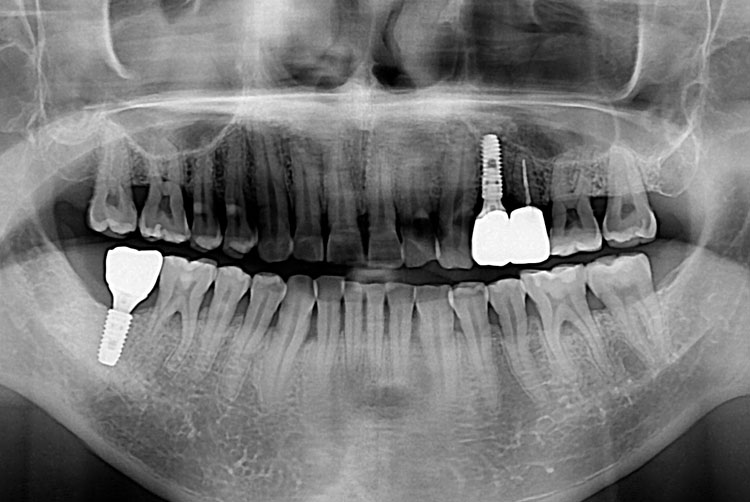

[임플란트] 임플란트

치료전 : 2018-05-16

세종치과는 많은 환자와 다양한 케이스를 바탕으로 항상 편안한 임플란트 수술을 제공하고자 노력하고,

오래동안 튼튼히 쓸 수 있는 임플란트 수술을 가장 큰 목표로 삼고 있습니다.